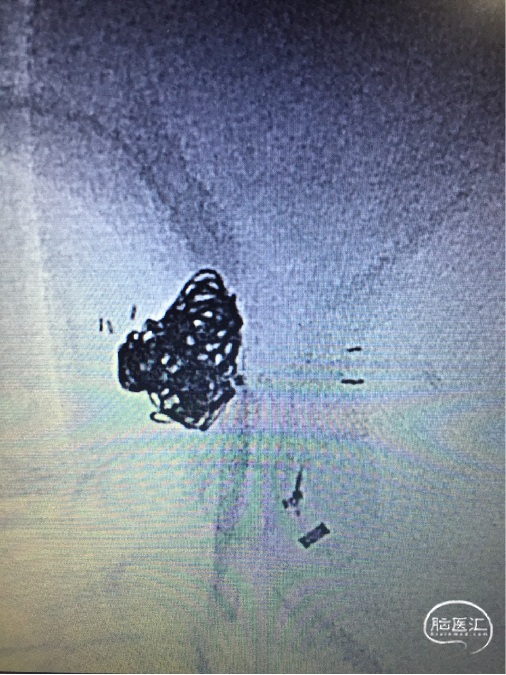

栓塞过程

直头SL-10及S头SL-10先后交互填圈,分区致密栓塞动脉瘤。

栓塞后即刻影像

工作角度造影显示动脉瘤栓塞致密,LACA A1、ACoA、双A2显影良好,左A2似有血栓(左图)。直头SL-10退至LACA A1末端,推注替罗非班1ml(右图)。

术后支架重建及蒙片:显示支架完全打开,贴壁充分,动脉瘤栓塞致密。